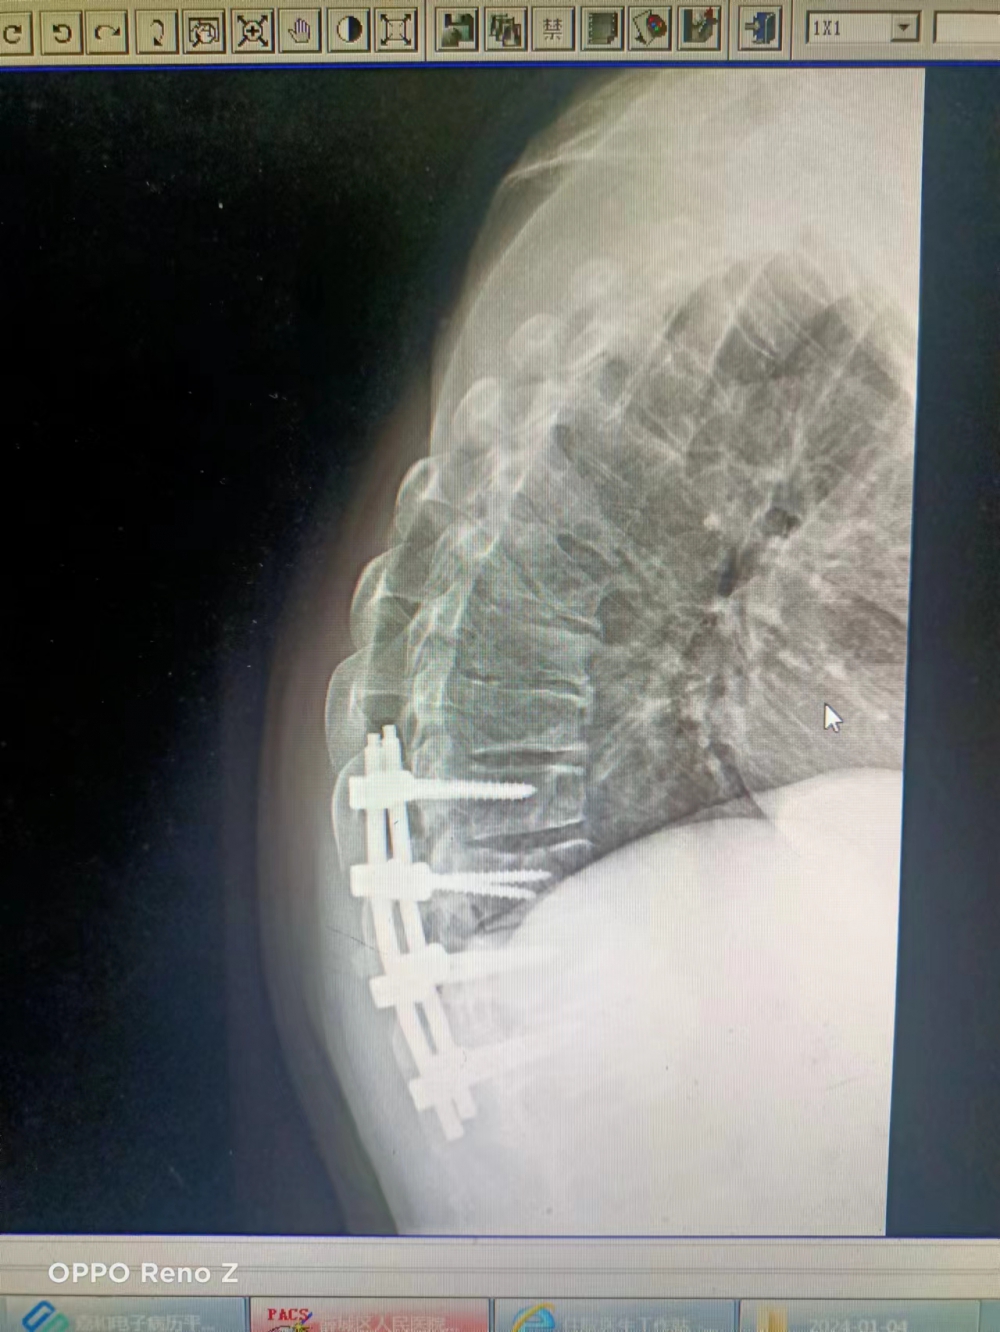

患者孟某于1月3日因高處墜落傷,疼痛難忍,肢體活動(dòng)障礙來(lái)院就診。入院后診斷為胸椎多發(fā)性壓縮性骨折,合并脊柱側(cè)彎、胸腔積液、勒骨骨折、肺挫傷,手術(shù)治療難度較大,易損傷脊髓和神經(jīng)??浦魅蚊蠎c濤帶領(lǐng)脊柱外科團(tuán)隊(duì)共同討論并制定詳細(xì)手術(shù)方案,決定行后路T10、T11、T12骨折切開(kāi)復(fù)位椎弓根螺釘內(nèi)固定術(shù)。經(jīng)過(guò)充分術(shù)前準(zhǔn)備及完善手術(shù)預(yù)案后,手術(shù)于1月20日成功完成,胸椎高度基本恢復(fù),未出現(xiàn)并發(fā)癥,患者對(duì)術(shù)后恢復(fù)情況非常滿意。這也代表我院脊柱外科在胸椎領(lǐng)域技術(shù)水平得到很大提升。